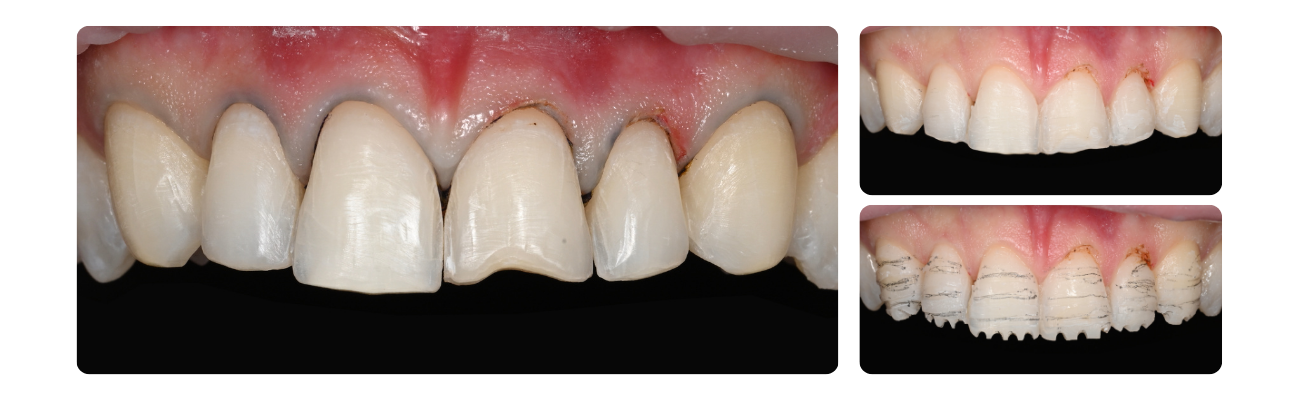

E I N D R E S U L T A A T   &   D O C U M E N T A T I E

Na de plaatsing van de definitieve restauraties voeren we meerdere weefselcontroles uit om de gezondheid van het tandvlees te waarborgen. Deze afspraken gaan gepaard met definitieve foto's van ons werk — het meest bevredigende deel van dit proces.

Eindresultaat & Documentatie